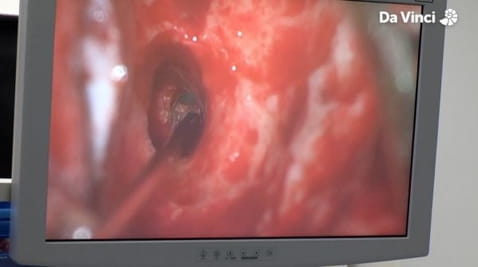

4. Komory mózgowe i połknięta kamera

10. Widok z wnętrza jelit